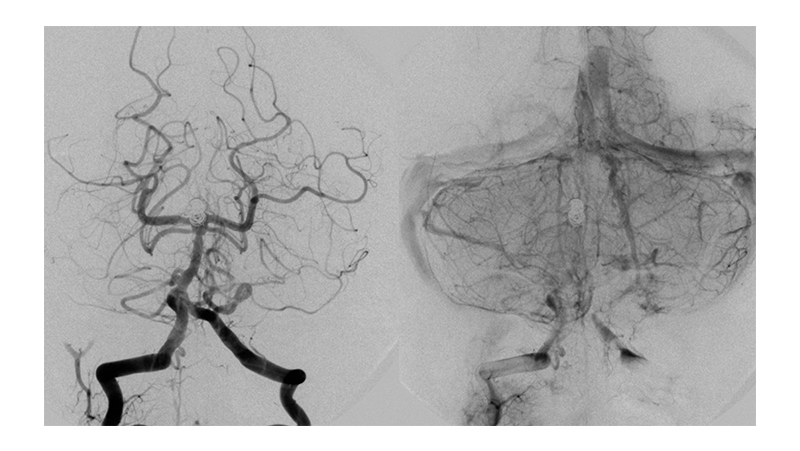

Εικόνα 1: Μη ραγέν ανεύρυσμα της κορυφής της βασικής αρτηρίας, το οποίο έχει ευρύ αυχένα.

Στην διαμόρφωση του αυχένα συμμετέχουν τα Ρ1 τμήματα των οπισθίων εγκεφαλικών αρτηριών αμφοτερόπλευρα.